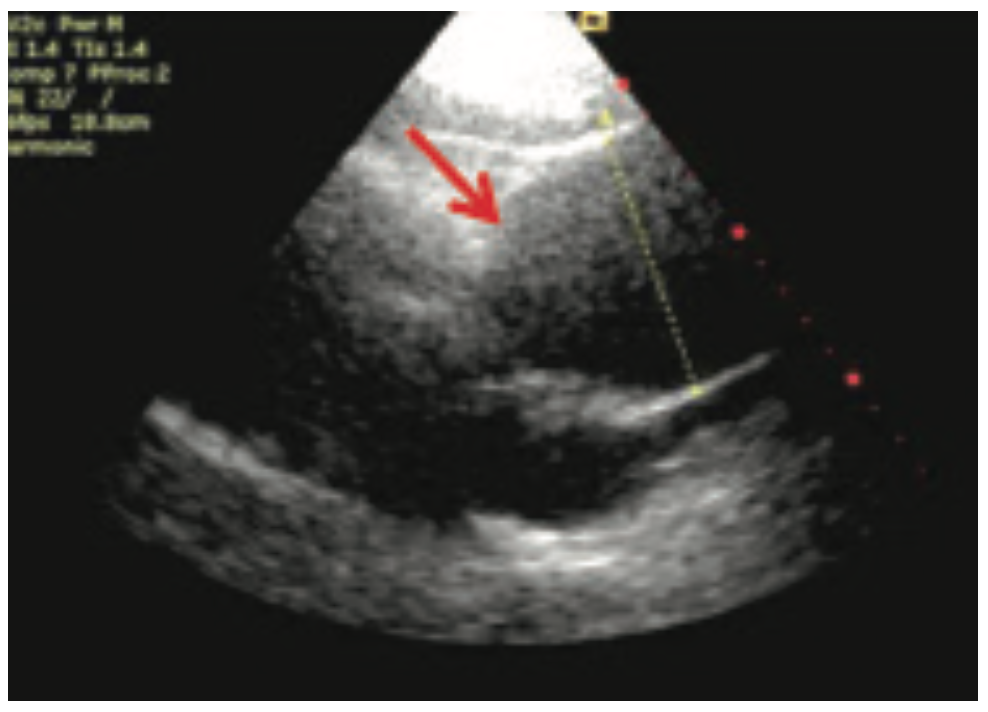

Infected Aneurysm and Inflammatory Aorta Diagnosis and Management IntechOpen

From www.cureus.com

Cureus Point of Care Ultrasound Diagnosis of a Massive Thoracoabdominal Aortic Aneurysm How Is An Enlarged Aorta Diagnosed Most aortic aneurysms are aaas, located in your belly. How big is too big? an abdominal aortic aneurysm is an enlarged area in the lower part of the body's main artery, called the aorta. When should i be worried? how is aortic aneurysm diagnosed? Many aneurysms develop without causing symptoms. if you’ve been diagnosed with an enlarged. How Is An Enlarged Aorta Diagnosed.